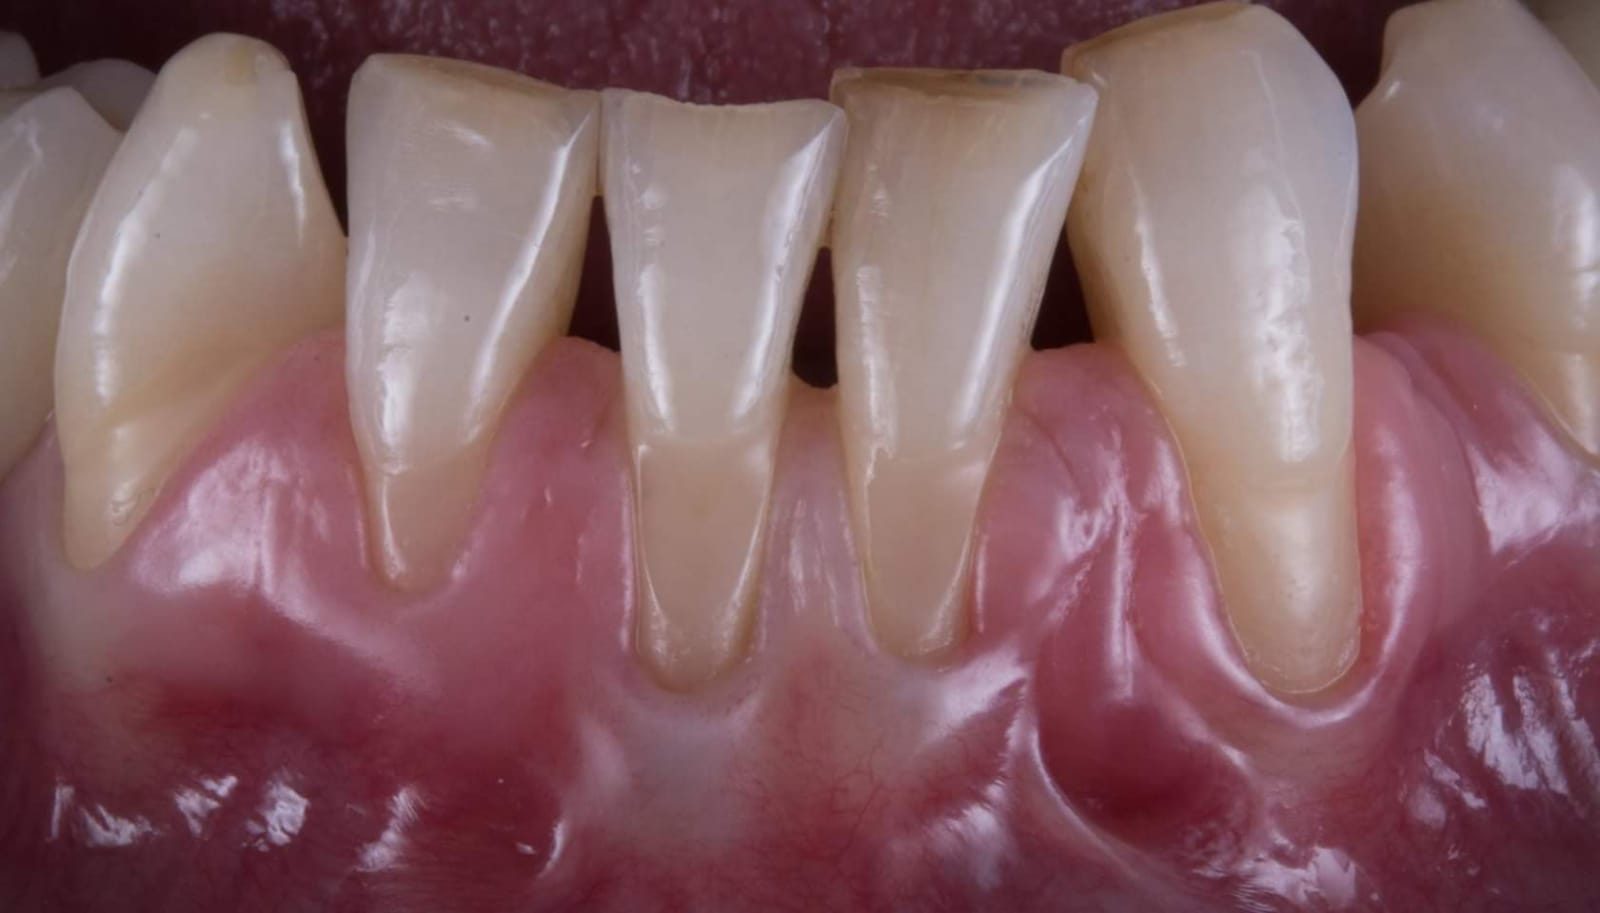

Il caso era questo.